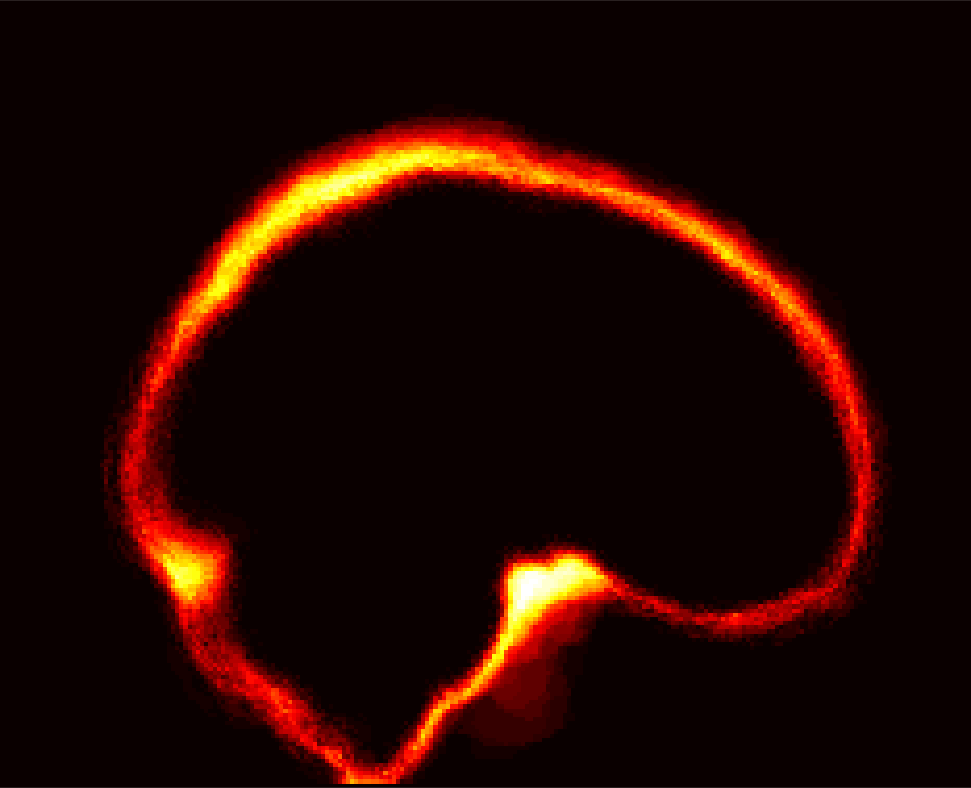

Fig. 1 shows example images from each dataset to illustrate image variability. IBSR and LPBA40 contain images from normal subjects and include large portions of the neck; BRATS has very low out-of-plane resolution; and the TBI dataset contains large pathologies and abnormal skulls.

Refer to caption

Figure 1: Illustration of image appearance variability on a selection of images from each (evaluation) database. From top to bottom: IBSR, LPBA40, BRATS and TBI.